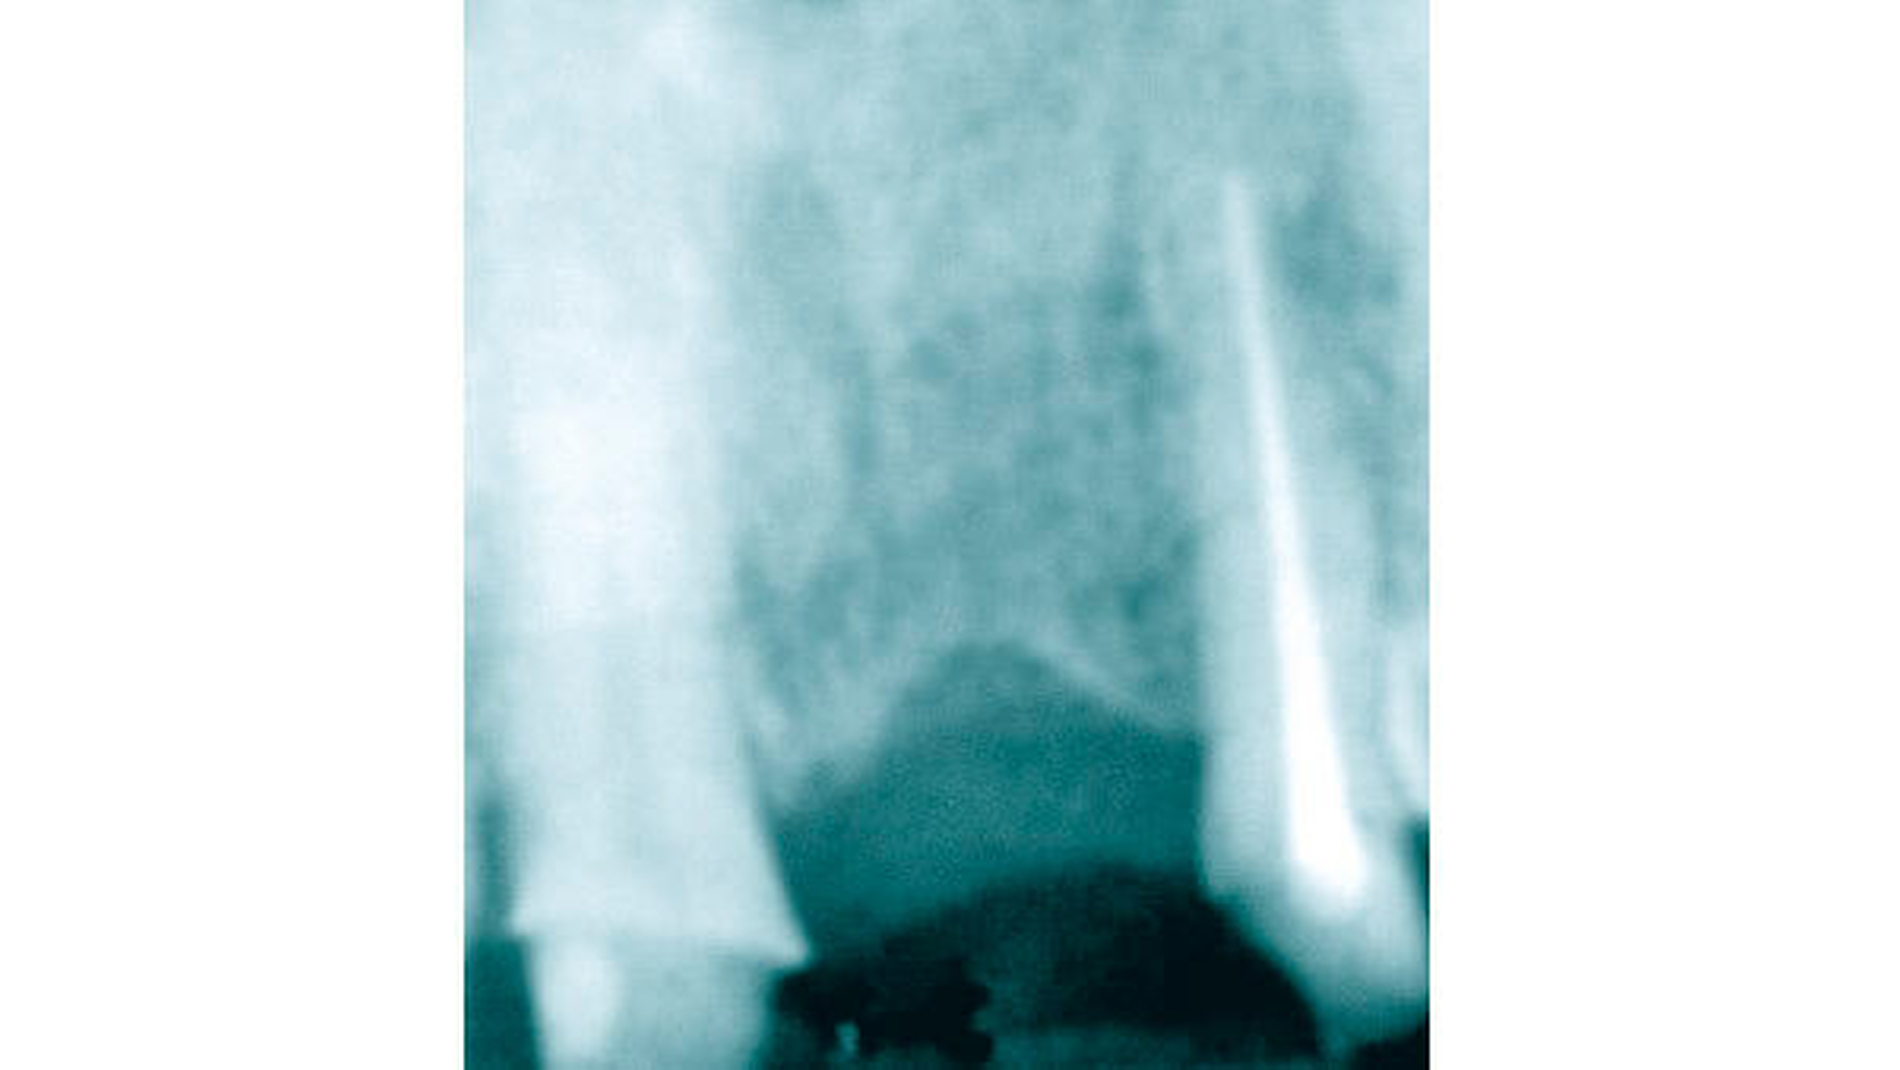

Nachdem im Rahmen einer Gesamtsanierung Zahn 21 nicht erhaltungswürdig gewesen ist, erfolgte eine forcierte Extrusion beginnend mit rund 700 cN mit zwei Gummiwechseln innerhalb von zwei Tagen und anschließend eine komplett noninvasive Entfernung des Zahnes.

Direkt unterhalb des Zahnhalses wurde eine etwa 2,5 bis 3 mm dicke Wurzelscheibe abgetrennt und genau an ihre ursprüngliche Stelle so replantiert, dass das umliegende Weichgewebe „wie gewohnt“ protektiv gestützt wurde (Abbildung 13). Die Vorhersagbarkeit dieser Methode konnte auch durch einen etwas außergewöhnlichen, weiteren Fall verifiziert werden: Entgegen unserer Vorgabe, sich etwa sechs Wochen nach der Replantation der Wurzelscheibe erneut vorzustellen, erschien die Patientin erst fünf Jahre später wieder in der Praxis und selbst nach diesem langen Zeitraum war der bukkale Knochen unter der replantierten Wurzelscheibe vollständig erhalten geblieben (Abbildung 14).

Unter der replantierten Wurzelscheibe an Zahn 21 (Abbildung 16) erfolgte in nur acht Wochen eine vollständige Knochenregeneration der Alveole. Dabei blieb auch der bukkale Hart- und Weichgewebsanteil vollständig erhalten. Nach Entfernung der Scheibe war für eine optimale Positionierung des Implantats in allen Dimensionen ausreichend Knochen vorhanden (Abbildungen 17 und 18).